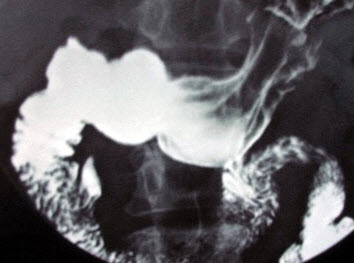

120、单项选择题

男,75岁,吞咽困难3月,伴胸痛,结合图像,最可能的诊断为()

A.贲门癌

B.胃底癌

C.食管下段癌

D.贲门癌侵及食管、胃底

E.食管胃底静脉曲张